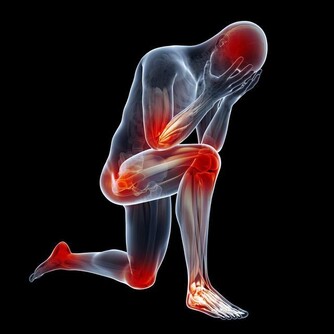

【早安健康/翁浩雯編譯】當坐骨神經痛開始發作時,灼熱的疼痛、刺痛感或是麻痺感從下背部延伸到你的其中一隻腳,確實會使人亟欲尋找解決疼痛的方法。以下介紹簡單的伸展動作,不僅可以降低坐骨神經的壓力,而且在床上就能做。 一位華盛頓大學物理治療系的教學助理,珍妮佛 .豪威,研發出以下伸展動作。可以舒緩造成坐骨神經痛的三種主要原因:椎間盤突出、骨骼退化和大腿肌肉過緊。 如果你不確定究竟是什麼原因造成坐骨神經痛,試試看這三套緩和動作。每天在早上起床之前,或晚上睡前,都可以做伸展運動,達到最好的效果。如果你願意的話,在地板上也能夠進行。 椎間盤突出 以下的兩個伸展動作可以拉開椎間盤之間的空隙,讓坐骨神經的壓力降低。 一、臥撐 1. 手肘垂直放在肩膀下方,兩隻前臂平貼在床上,互相平行。 2. 抬起你的胸膛,然後延伸尾骨到脖子這段脊椎,讓你的背部呈現弓箭型。 3. 一次要撐住30秒,一邊深呼吸。如果你腿部的疼痛有所減緩,再重複做兩次,接著做下一個動作。但你若感到不舒服,就跳過這個動作,試試看針對骨骼退化的伸展動作。

大腿肌肉緊繃 以下兩種伸展動作能使壓迫到坐骨神經的大腿肌肉放鬆。 一、膝蓋拉向另一邊的肩膀 1. 將你的背部放平,雙腿伸展,一腳彎曲。 2. 舉起右腳,手抱住膝蓋後方。 3. 慢慢地將你的右膝跨過身體,往左肩的方向施力。 4. 一次要維持30秒,做三次之後,換腳並重複剛才的動作。

二、「4」字型伸展 1. 背部平躺,膝蓋彎曲,腳掌平貼在床上。 2. 將右腳踝放在左膝蓋上,形成「4」字型。 3. 雙手繞到左膝後方,慢慢將兩隻腳拉近胸部,但是右膝朝反方向出力,推離胸部。 4. 一次動作要維持30秒,做三次之後,換腳後重複動作。